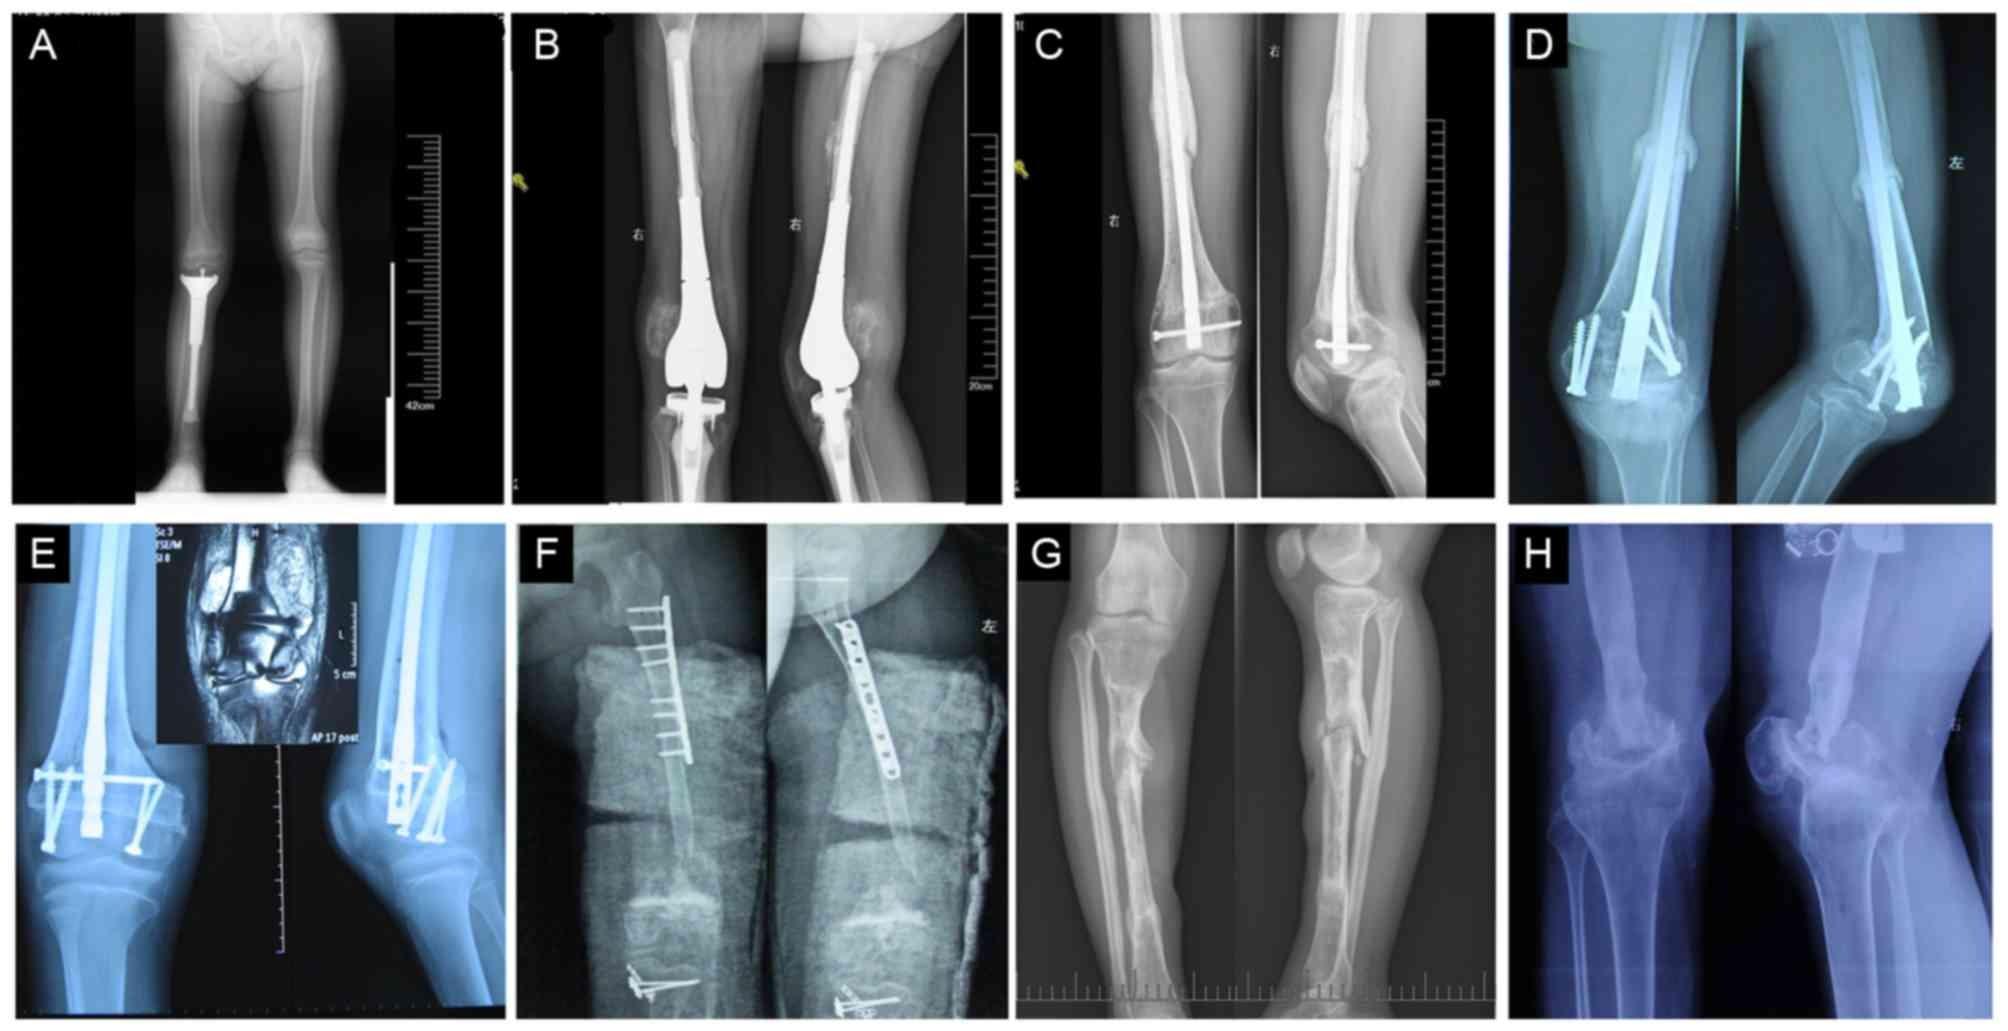

• Imaging tests like X-rays, CT scans, MRIs, or PET scans

Surgical intervention is often necessary to remove cancerous tumors from the bone. Surgeons aim to preserve limb function whenever possible through limb-salvage procedures. In more severe cases, amputation may be considered, though this is less common today thanks to medical advancements.